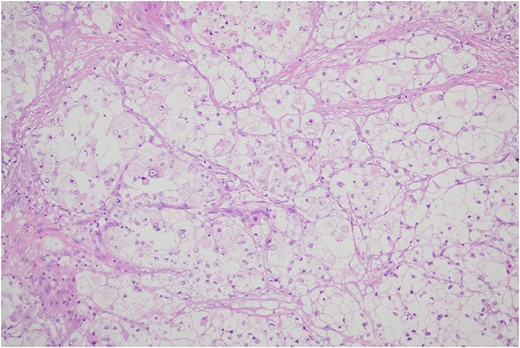

Histologic sections of the mass show distinct variably sized and shaped collections of uniform polygonal tumor cells, separated by fibrovascular septa and delicate capillary-sized vascular channels lined by flattened endothelium at low magnification (Fig. 5). Within the tumor nests, there is loss of cellular cohesion and necrosis of the centrally located cells in the nests results in the pseudo-alveolar pattern (Fig. 6). Vascular invasion is also present (Fig. 7). The individual tumor cells have distinct cell borders and abundant eosinophilic to clear, somewhat granular cytoplasm surrounding a central nucleus with variably sized nucleolus. Nuclear atypia is rarely seen. Mitotic figures are uncommon. The cells contain rhomboid or rod-shaped crystalline inclusions that are faintly apparent on routine histology and are better demonstrated with periodic acid-Schiff stain after diastase digestion (Fig. 8).

Loss of cellular cohesion and necrosis of the centrally located cells in the nests.